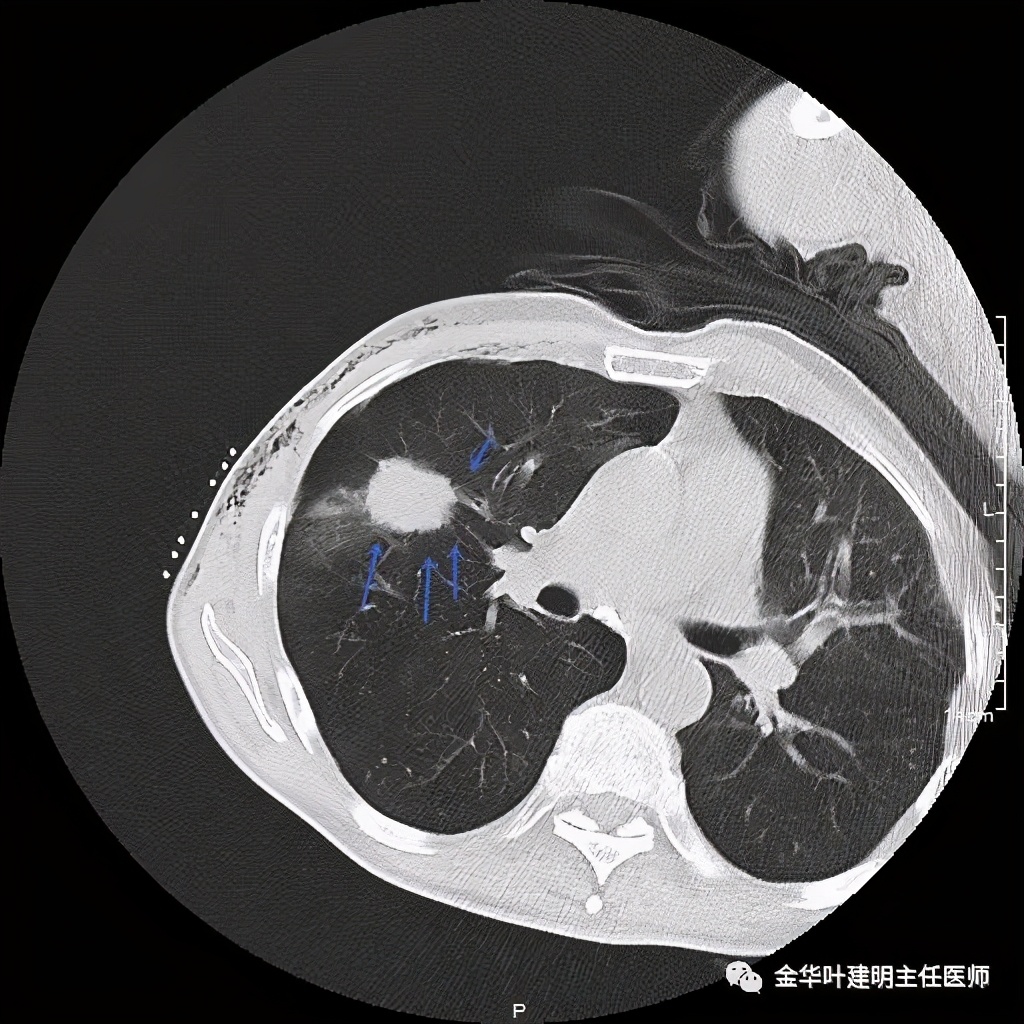

金华的某A,今年73岁,男性。检查发现右上肺占位,肿瘤筛查指标正常,血常规与CRP正常,临床有反复咳嗽、咳痰2年余(考虑慢支的关系,近期也许同时有病灶的影响)。一年前还在外院做过支气管镜,也未见确切异常。我们先来看他这次的胸部CT图像:

上图示病灶

上图桔色箭头示血管进入病灶,较粗;紫色箭头示病灶与胸膜间似乎有所牵拉;红色箭头示病灶

上图桔色箭头示血管进入;红色箭头示病灶

上图示病灶边缘不太光整,内部密度不太均匀

上图紫色箭头示叶间胸膜受牵拉,病灶边缘部分见到细毛刺